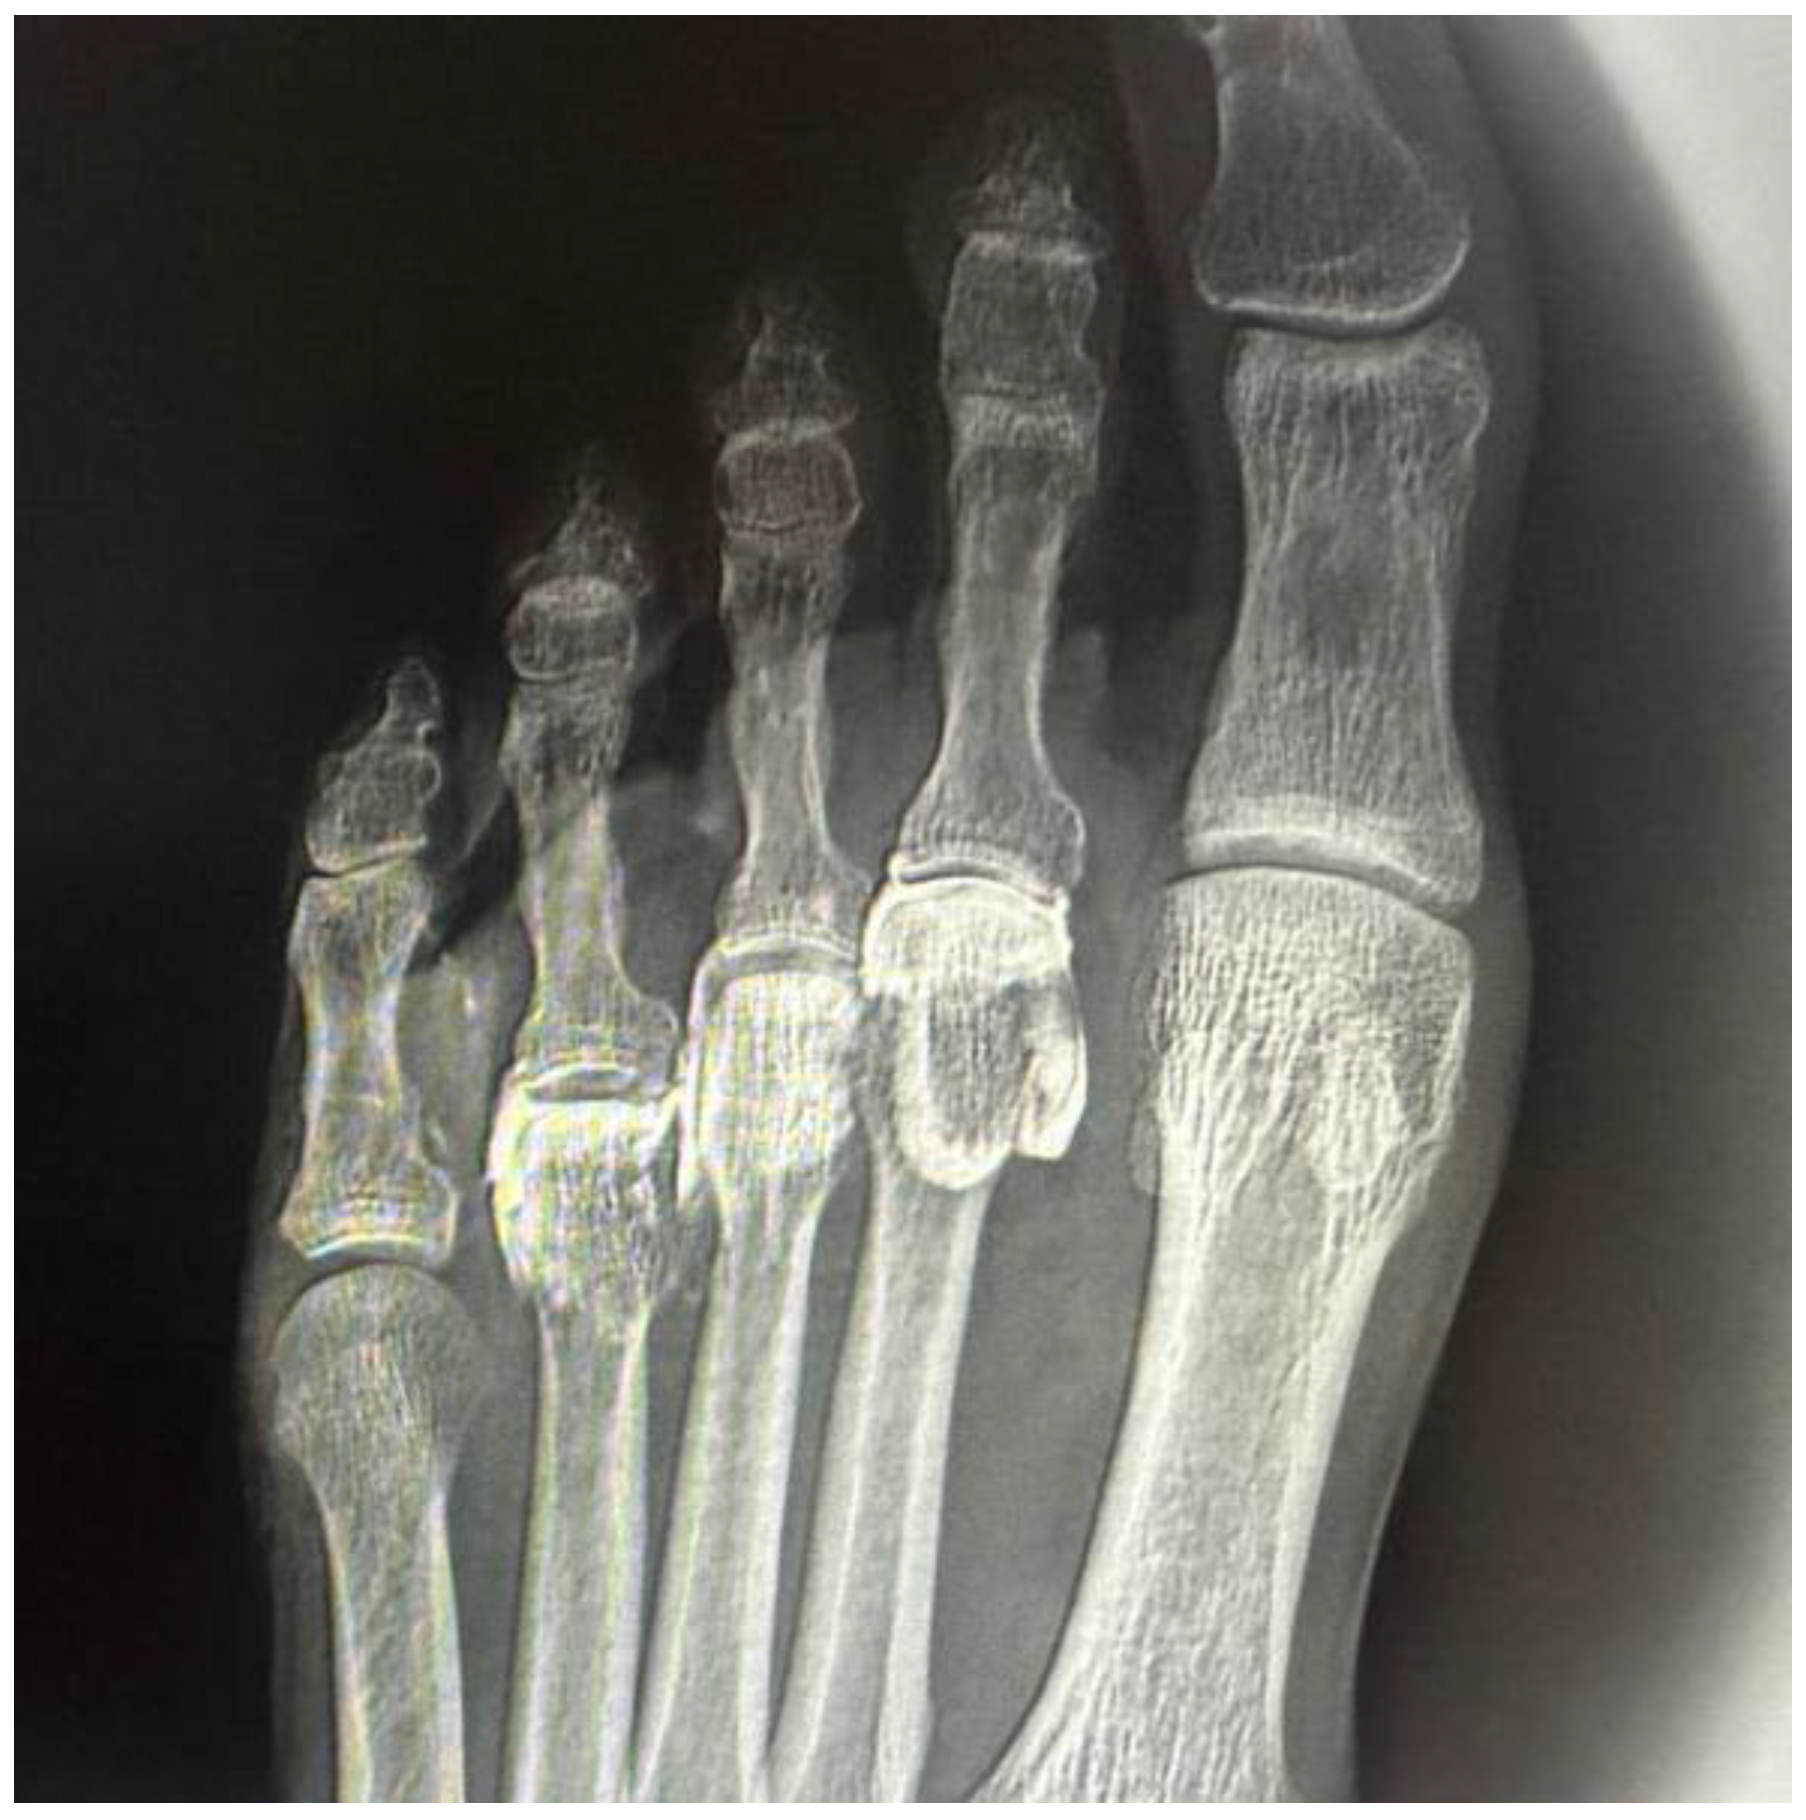

In all intra-articular injections (n = 12), iodinated contrast dispersion remained confined within the articular capsule (Figure 3). Radiographic images revealed a contained, symmetrical pattern with sharply defined margins and an ovoid or triangular morphology, depending on the projection plane. The distribution of contrast was homogeneous in all joints, with no evidence of extravasation into the collateral ligaments, dorsal capsule, or pericapsular regions. These findings support the hypothesis that the MTP joint functions as a closed, sealed cavity, offering a significant anatomical advantage for performing selective and reproducible diagnostic blocks.

Figure 3. Dorsoplantar radiograph of the right forefoot following intra-articular injection of radiopaque contrast. A volume of 0.5 cc was injected into the second metatarsophalangeal joint, 0.4 cc into the third, and 0.3 cc into the fourth. Complete filling of the joint cavities is observed without contrast extravasation, confirming the sealed capsular nature of each articulation.